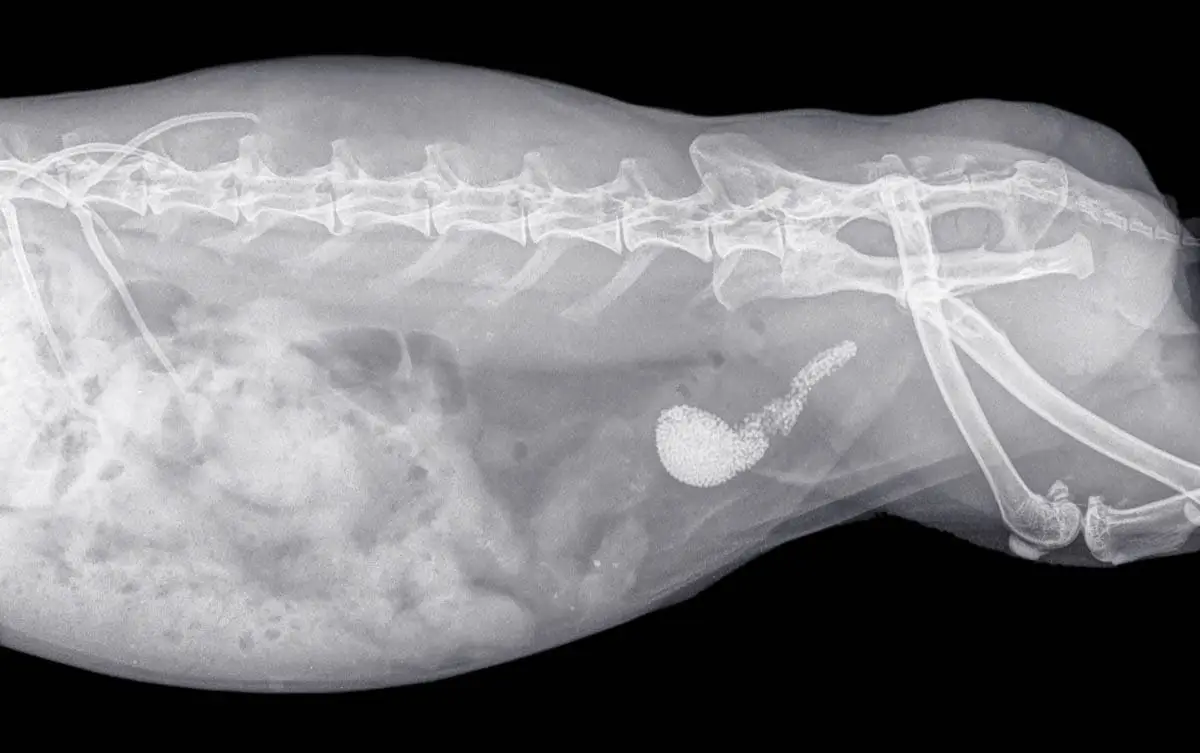

- Rayos X o ultrasonido para evaluar piedras, anomalías congénitas y tumores.

Su veterinario debe poder hacer un diagnóstico provisional basado en la presentación de síntomas. Realizará un examen físico completo cuando pueda sentir una vejiga firme y completa, también habrá dolor o incomodidad abdominal.